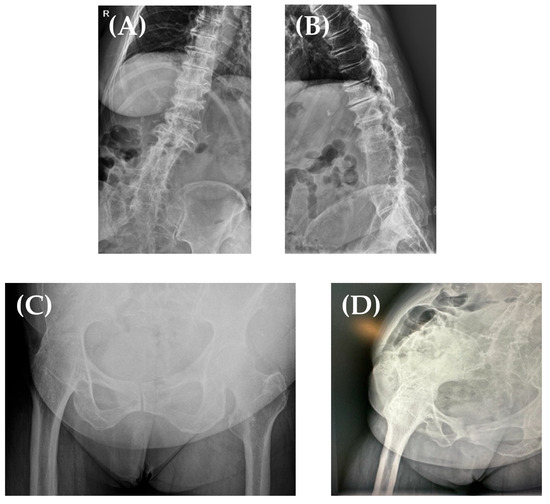

In 2018, a 75-year-old female patient who underwent right hip fusion at the age of 15 due to bacillary osteoarthritis was admitted to our clinic. She complained of severe pain and a significantly decreased range of motion (ROM) in her right (ipsilateral) knee; the patient was ambulating with the aid of crutches. The clinical examination of her right knee (Figure 1) revealed a right knee flexion of 90°, a 15° flexion contracture, and no mediolateral ligamentous instability. Her fused right hip was fixed in a flexion of 15°–20°, neutral abduction/adduction, and neutral internal/external rotation; she did not report any pain/discomfort in this hip. Her leg length discrepancy was measured at 3 cm, and she compensated for it with custom insoles.

Figure 1. Right hip fusion, with the hip fused in 15° HF (A), neutral HA, and neutral HER (B). Right knee flexion of 90° (C) and 10° of flexion contracture (D).